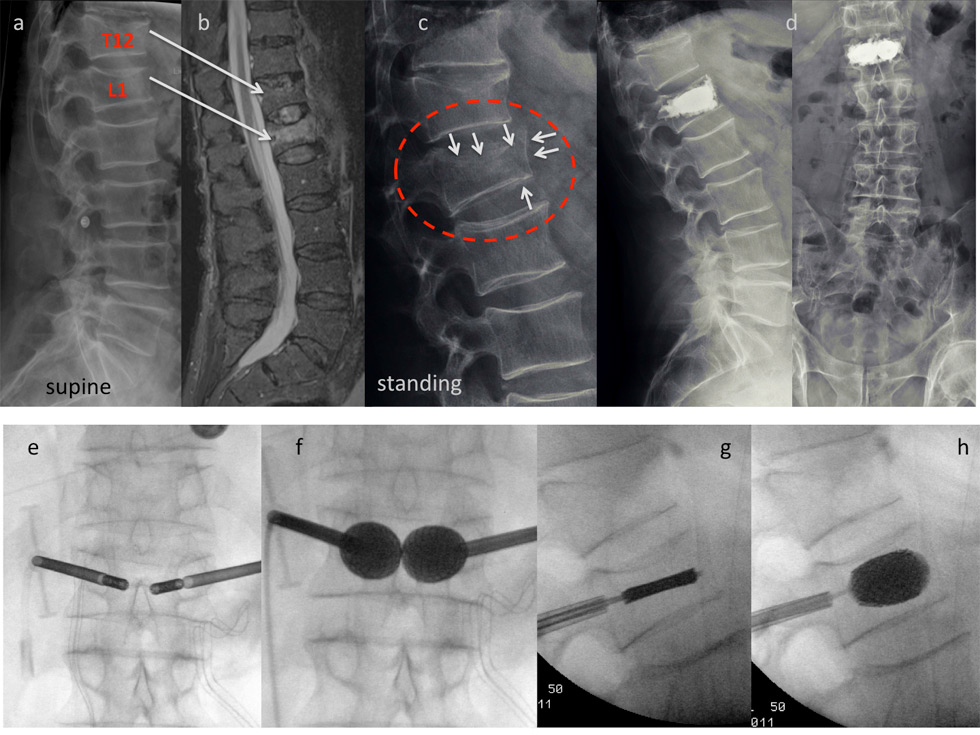

Case report stentoplasty: This 77-year-old male patient is referred to the emergency room after a fall from some 1.5 m. He presents with acute immobilising back pain. The x-ray taken in the supine position depicts fractures of T12 and L1 (a). The MRI scan discloses a fresh fracture of L1, whereas T12 appears old (b). The fracture was considered simple and conservative treatment was initiated with in- hospital physiotherapy and pain medication. After 3 days a standing X-ray was performed which shows a much more complex lesion in comparison to the initial pictures (white arrows): There is a split fracture with anterior wall displacement, and also the upper endplate has subsided considerably (c). A stentoplasty procedure was performed in local anesthesia, which did provide good height restoration and immediate stabilisation (d). The intraoperative pictures demonstrate complete restoration of the vertebral body’s shape (e-h).